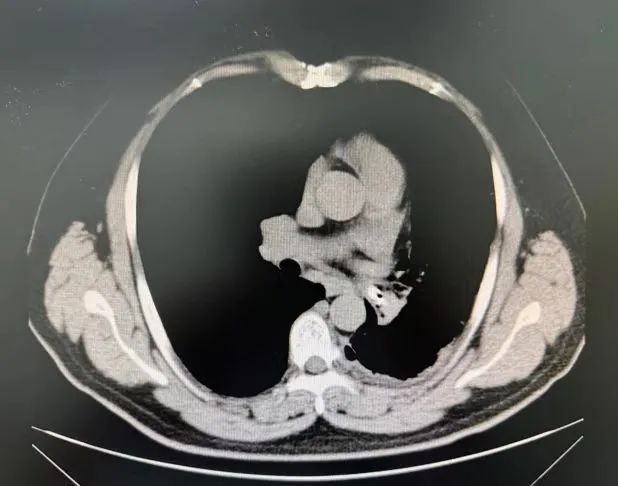

今年49岁的张先生(化名)长期饱受咳嗽、咳痰、呼吸困难的折磨,曾多次在外地医院治疗,效果不佳。近期症状加重,慕名来到哈医大一院群力院区呼吸内科于世寰教授处就诊。肺部CT检查结果令人惊讶:患者左侧气胸、左肺下叶支气管内存在可疑高密度异物阴影,并伴有阻塞性肺炎,遂急收入院。

该患者左肺下叶支气管内可疑的异物需利用呼吸内镜技术取出,但患者呼吸困难较重,肺功能很差,行支气管镜检查可能使气道压力出现变化致气胸加重,呼吸功能可能更加恶化,另外气胸患者肺组织受压后可能造成支气管镜下视野受限,因此为患者拟进行“支气管镜下异物取出术”的操作难度和风险极大。

手术当天,于世寰主任医师、李世敏副主任医师在全身麻醉保障下为患者进行手术。术中发现,患者左主支气管远端因长期异物刺激,已形成大量肉芽组织增生及瘢痕,导致管腔严重狭窄,大量脓性分泌物淤积。清除脓液后,镜下可见部分异物,但因管腔狭窄(直径小于4.2mm支气管镜),常规方法难以取出。李世敏医生谨慎运用氩气刀、电凝棒及活检钳等设备,耗时近3.5小时,逐步清除覆盖在异物周围的增生肉芽组织和瘢痕(术中需精细操作以避免出血),最终成功利用异物钳取出一枚完整的塑料笔帽。